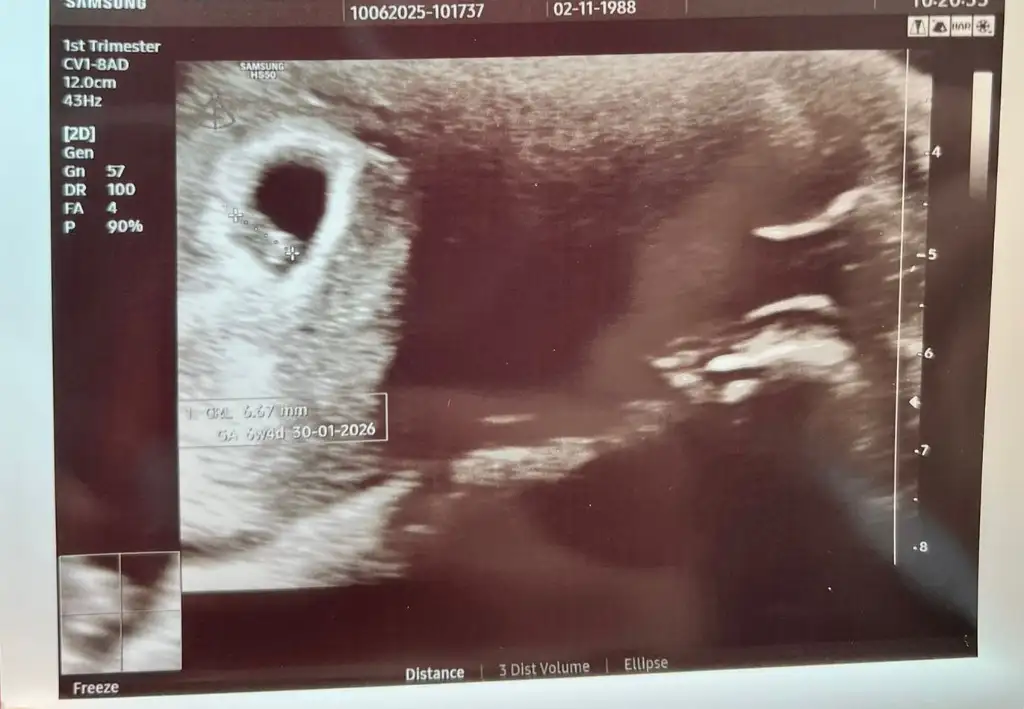

Merhabalar benimkinide yorumlar miiniz eklesemHayır karıştırdınız sanırım diğer hanımefendi yazmıştır 1 kızım var benim

Erkek bebek

Teşekkür ederim birkac kişi de kiz dedi neye göre oluyor anlayamadımErkek bebek

Cinsiyeti belli olunca yaz merak ettimTeşekkür ederim birkac kişi de kiz dedi neye göre oluyor anlayamadım

Bebek 22 haftalık oldu devlet hastanesine gidiyorum ters bebek dedi o yüzden anlayamadım diyor. Ters bebek ne oluyorsa anlamadım benBurda kafa şekli erkek bebek belli olmuştur artık 14 haftalıksiz söyleyin

Ters duruyordur canım da o bahane devlet hastanesi söylemiyor erken yapıyor öyleBebek 22 haftalık oldu devlet hastanesine gidiyorum ters bebek dedi o yüzden anlayamadım diyor. Ters bebek ne oluyorsa anlamadım ben